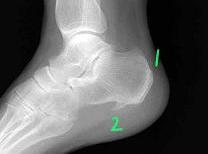

1、アキレス腱付着部または踵骨後面の骨端炎 腓腹筋(ふくらはぎ)につながるアキレス腱の付着部に起こる炎症です。写真1の部位に靴が当たったり、またはスイングで足の蹴りが強かったりして負担がかかると炎症を起こします。またgolfのやりすぎによる疲労も原因になります。 またこの部位での炎症は痛風の発作も考慮しなければなりません。痛風による炎症は、炎症症状が強いのが特徴です。痛みが激しく、赤くはれ、熱感を伴います。痛風発作の際でも必ずしも血中尿酸値が高くなっているとは限りません。痛風による踵骨骨端炎でも、機械的な刺激による踵骨骨端炎でも炎症を抑えるための治療を行ないます。痛風の場合はコルヒチンの投与、長期で定期的な管理などが必要となります。

1、アキレス腱付着部または踵骨後面 2、踵骨足底部の骨棘